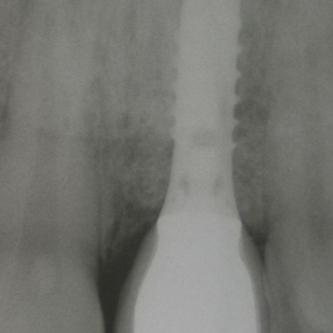

Exemple 14: Il est prévu de mettre un implant entre la molaire et prémolaire, mais le sinus se trouve à moins de 4 mm de la surface. Il faut donc relever le sinus avec une greffe d'os

Exemple 14: Un petit puits d'accès est créé afin d'atteindre le sinus, notez la membrane sinusienne.

Exemple 14: La fine membrane sinusienne est relevée, puis de l'os mélangé à de l'os artificiel est introduit dans la cavité.

Exemple 14: La cavité est maintenant remplie.

Exemple 14: Radiographie post chirurgicale.

Exemple 14: 6 mois plus tard, l'implant est introduit dans cette greffe sans toucher le sinus.